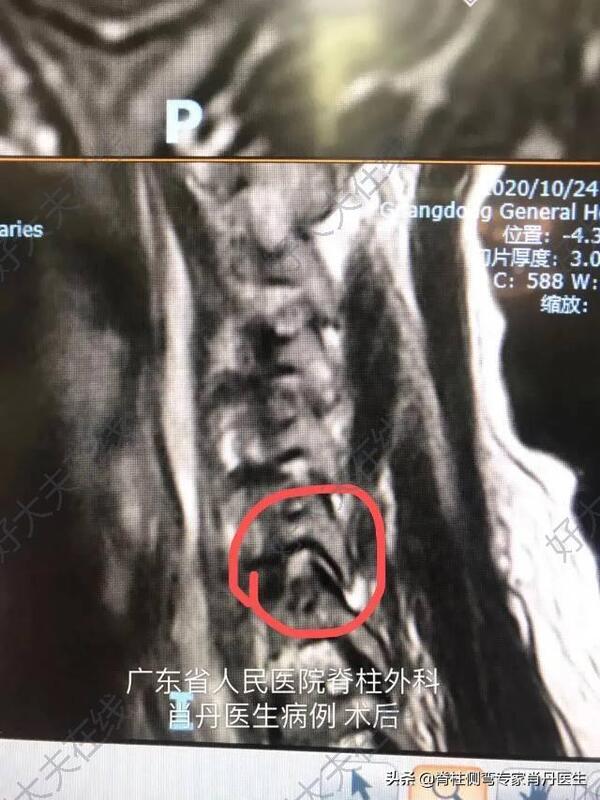

老年女性患者,左侧颈肩疼痛两周,保守治疗不能缓解,严重影响生活质量,核磁共振显示C67椎间盘突出压迫神经,诊断神经根型颈椎病